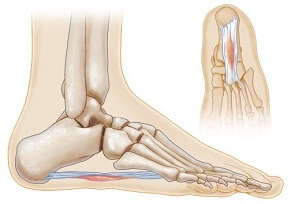

Inflammation and damage to the thick band underneath the foot, the plantar fascia

Causes: Muscle tightness, flat feet, overuse, sudden increase in activity, poor foot wear

Symptoms: Pain on bottom of foot and around heel, worse when on tiptoes or when you start walking

Full Article: Plantar Fasciitis